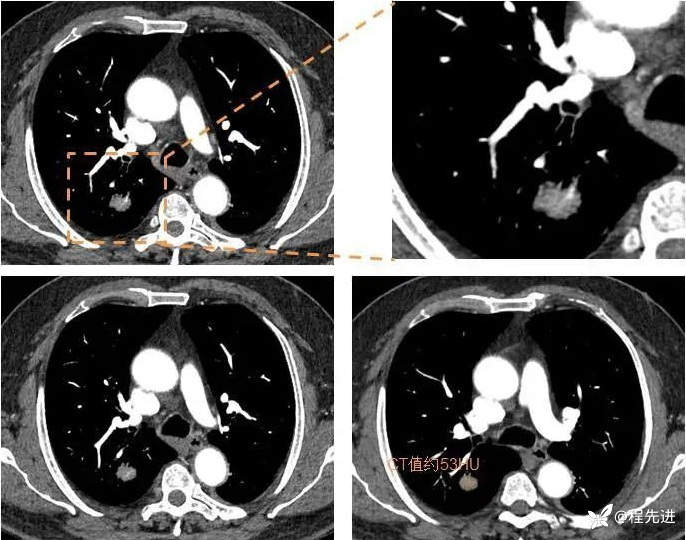

动脉期

静脉期

来个特写